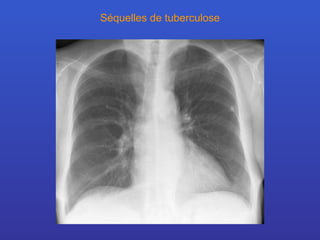

Séquelles de tuberculose